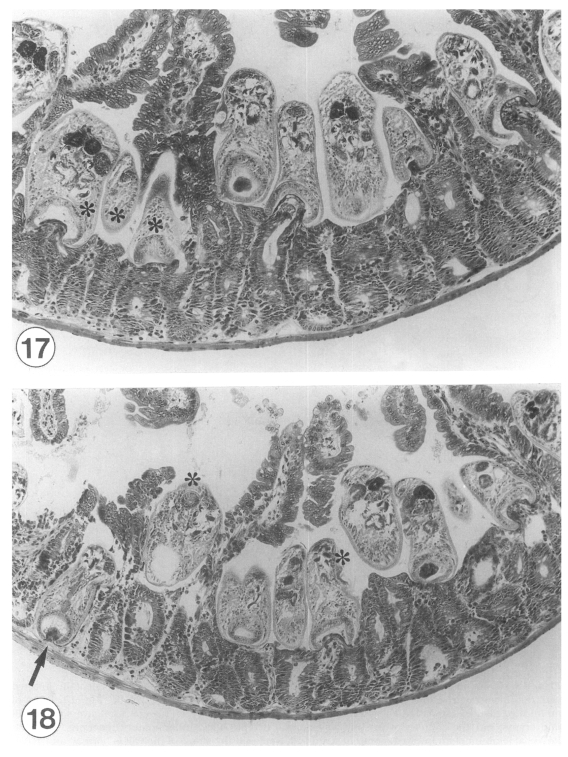

Intestinal histopathology and in situ postures of Gymnophalloides seoi in experimentally infected mice

The Korean Journal of Parasitology 2001;39(1):31-41.